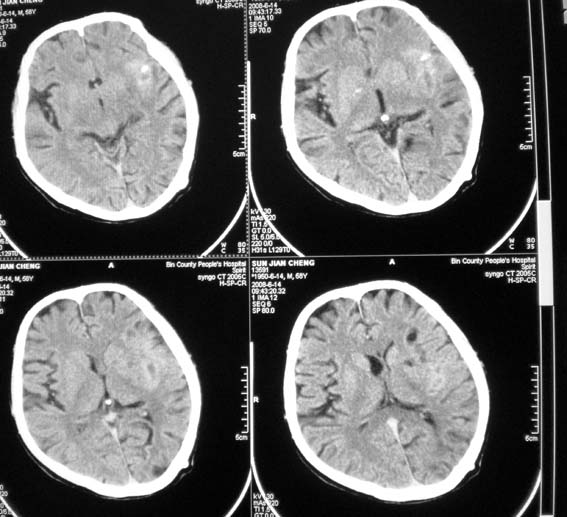

以下是引用随光逐影在2008-6-15 17:27:00的发言:[br]1)脑积水引流术后导管留置。2)蛛网膜下腔出血。3)左侧基底节区及左侧额叶多发脑腔隙灶。4)脑萎缩。

以下是引用dyqct在2008-6-15 10:32:00的发言:[br]支持:1、左侧外侧裂池密度增高,考虑出血。[br] 2、左侧基底节区脑软化灶。